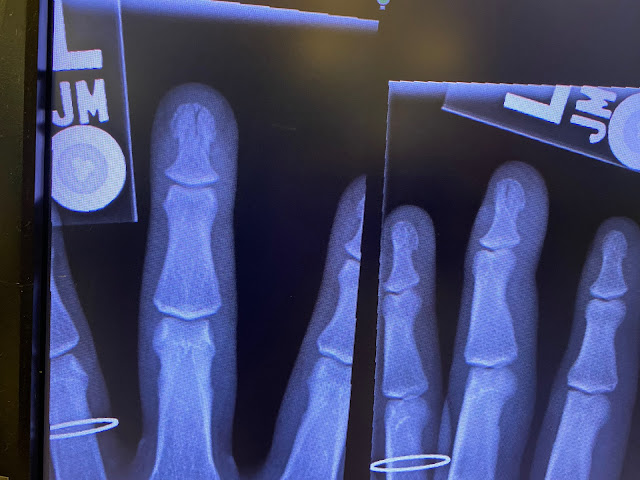

| Matt's fancy hammer betrayed him. |

| With one confident whack, the hammer smashed the tip of his middle finger. |

| Like a trooper he managed to finish the roof before going to the ER and he still worked on the shed all weekend. |